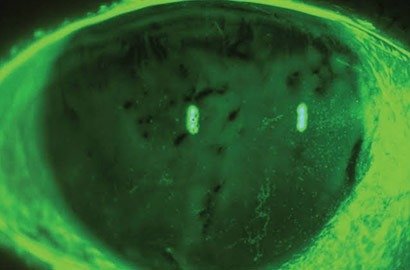

Retina Examination and Treatment

A retinal exam is essential for maintaining optimal eye health. During this examination, your eye care professional

Glaucoma Evaluation / Treatment

A group of eye diseases known as glaucoma affects the optic nerve, which is essential for transmitting visual data..